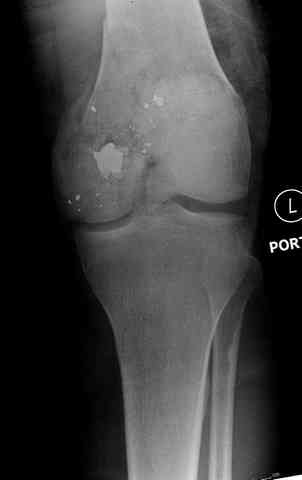

Пуля от ПМ - очевидно, что ранение было т.н. низкоэнегетическим, что подтверждается в том числе спокойным состоянием мягких тканей в этом, уже отсроченном периоде.

Здесь представлены несколько случаев лечения огнестрельного перелома

2 внутрисуставной перелом дистального бедра с удалением пули